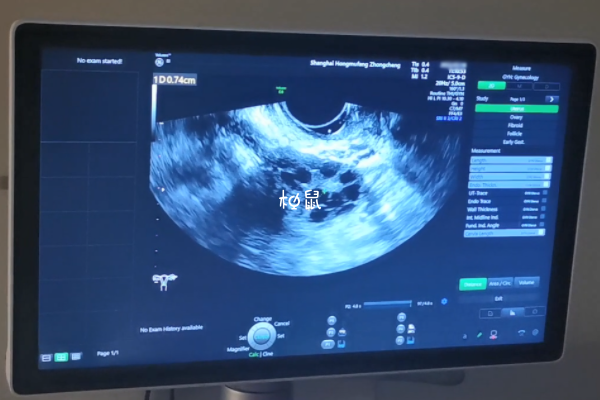

卵泡监测的最佳时间是在月经第十天左右,此时卵泡大小能够被B超所发现,此时监测也能了解卵泡发育速度,预估排卵时间。

阴超检查的方法和位置更贴近卵巢和子宫,通过阴超检测卵泡,能够更直观的观察到卵泡的发育程度。

去医院测排卵的时候要注意是否需要憋尿,如果是做阴超的话是不能憋尿的,腹部B超是需要憋尿才能知道卵泡发育情况的。